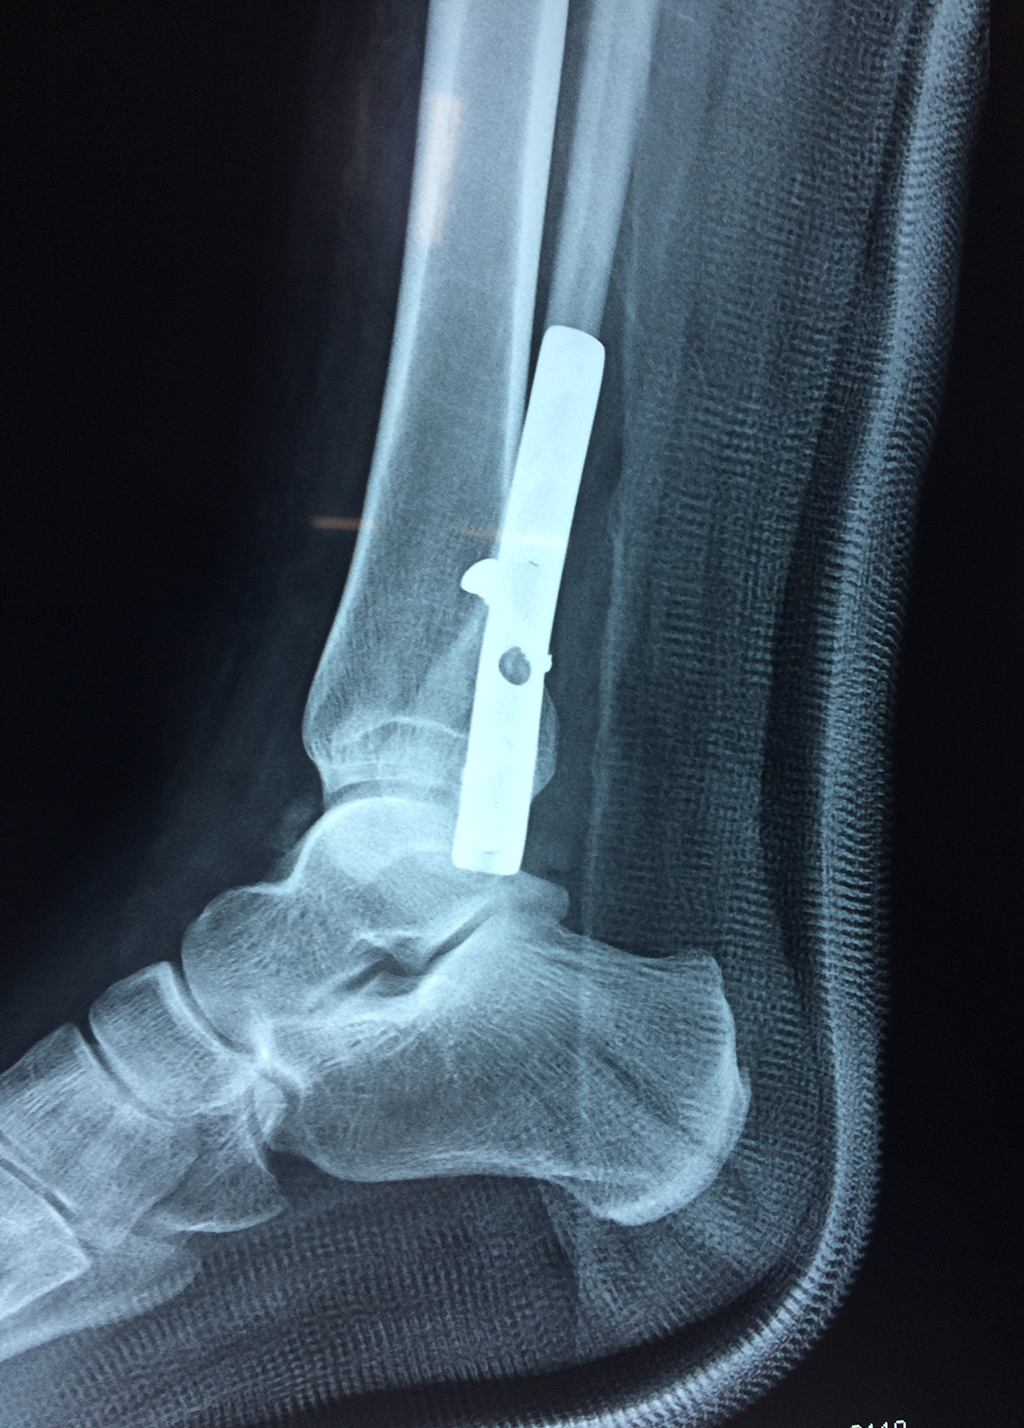

Cuando se necesita cirugía, es probable que esta implique el uso de clavijas de metal, tornillos o placas para sostener los huesos en su lugar mientras la fractura se consolida. Los elementos de soporte pueden ser temporales o permanentes.

Cirugía de Tobi...

Detail Download